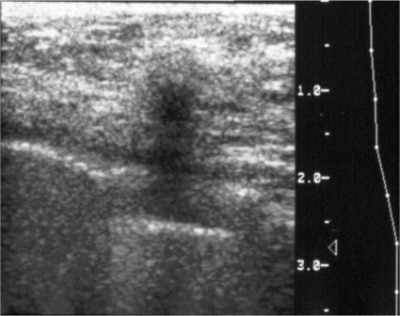

![]() |

| A large cancer is present in the image on the left, but the cancer cannot be seen because it is completely obscured by the dense glandular tissue around it. Note that the breast with the cancer looks exactly like the one without a cancer. The cancer was found here because it was palpable, and was visible on an ultrasound done at the same time as the mammogram. Image courtesy of Dr. Michael Linver. |

Ultrasound should not be ruled out in the young breast, though, said Linver. "If the patient is under 30, ultrasound would be the place to start," he said. "We can find breast cancers sometimes on ultrasound that we can’t find on mammography."

Although ultrasound is more sensitive than mammography, the down side is a risk of false positives, he said. "The big question regarding the cancers caught by ultrasound but missed by mammography is: at what price financially? The answer is, a lot. It costs a lot to do a screening ultrasound and an unnecessary biopsy. There are all kinds of reasons to avoid a screening ultrasound every year. Also, there are no controls over who can do a breast ultrasound, and, as radiologists, we know how important it is to have high-quality imaging."